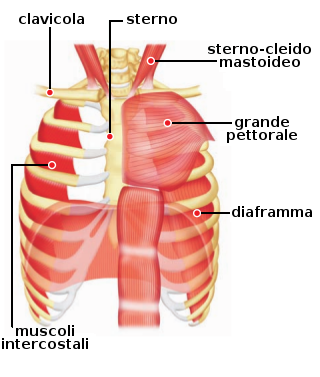

| Diaframma | È un muscolo scheletrico che divide il corpo in due cavità: la cavità addominale e quella toracica. | Durante la inspirazione, appiattisce e aumenta il diametro verticale della cassa toracica. |

| Muscoli intercostali | È un gruppo di muscoli che si trova tra le costole, in ambo i lati della cassa totacica | Si contraggono e si rilassano durante i movimenti respiratori. Al contrarsi aumentano il diametro anteroposteriore e trasversale della gabbia toracica |

Si denomina così il processo ciclico che mantiene costante la quantità di aria nei polmoni. Comporta due fasi: la inspirazione, che introduce l'aria atmosferica nei polmoni e la espirazione che la espelle. Per queste funzioni il sistema respiratorio conta sulle strutture annesse: il diaframma, i muscoli intercostali e i muscoli addominali sono quelli che svolgono le funzioni più importanti (vedi tabella qui sopra).

Il diaframma è un setto di tessuto muscolare e tendinoso che divide la cavità toracica da quella addominale. Le fibre muscolari periferiche si riuniscono in un tendine centrale, che è incaricato di andare verso il basso ed ampliare il volume della cassa toracica. Il diaframma presenta una serie di forami attraverso i quali passano diverse strutture come l'aorta, l'esofago, la vena cava inferiore.

I muscoli intercostali si trovano tra le costole e formano la parete toracica.

- INSPIRAZIONE: Quando inspiriamo, il diaframma e i muscoli intercostali esterni e interni si contraggono. Nella inspirazione forzata (provocata da una intensa attività fisica ed una alta esigenza respiratoria) intervengono inoltre i muscoli pettorali e gli sternocleidomastoidei.

Al contrarsi del diaframma, il suo centro scende verso il basso, il che produce un aumento verticale della cavità toracica, spingendo i visceri addominali verso il basso. La contrazione dei muscoli intercostali produce l'elevazione delle costole e la spinta in avanti dello sterno. In questo modo i diametri anteroposteriore e laterale aumentano, causando un aumento del volume polmonare. Questo aumento causa un vuoto che causa una differenza di pressione con la pressione atmosferica. In questo modo l'aria atmosferica entra per creare un equilibrio. - ESPIRAZIONE: Si produce quando il diaframma e i muscoli intercostali si rilassano (tornano alla loro posizione abituale). Questo significa che il diaframma si alza e i muscoli intercostali discendono, diminuendo il volume della cassa toracica, quindi dei polmoni stessi. La diminuzione del volume polmonare causa un aumento di pressione nei polmoni che porta l'aria ad uscire. Contribuiscono alla espirazione anche i muscoli addominali, che comprimono la cavità addominale spingendo i visceri verso l'alto contro il diaframma.